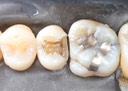

Joe Cha #18 pre-op

Joe Cha #18 composite removal

Joe Cha #18 prep